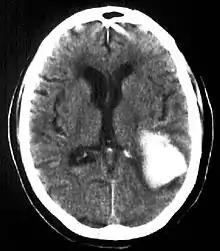

Intraparenchymal hemorrhage (IPH) is one form of intracerebral bleeding in which there is bleeding within brain parenchyma. The other form is intraventricular hemorrhage (IVH).[1]

Intraparenchymal hemorrhage accounts for approximately 8-13% of all strokes and results from a wide spectrum of disorders. It is more likely to result in death or major disability than ischemic stroke or subarachnoid hemorrhage, and therefore constitutes an immediate medical emergency. Intracerebral hemorrhages and accompanying edema may disrupt or compress adjacent brain tissue, leading to neurological dysfunction. Substantial displacement of brain parenchyma may cause elevation of intracranial pressure (ICP) and potentially fatal herniation syndromes.